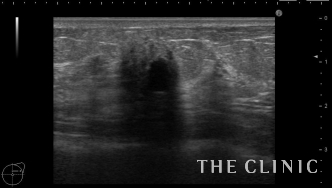

大きなしこりはありませんが、エコーでは多数のオイルシストと石灰化を認めました。

これは壊死した脂肪による石灰化です。マンモグラフィーでは粗大な石灰化で良性と診断されます。

このしこりは石灰化の近くにオイルシストを認めます。

オイルシスト部分のみを穿刺吸引しましたが、ある程度はしこりを触れにくくなります。